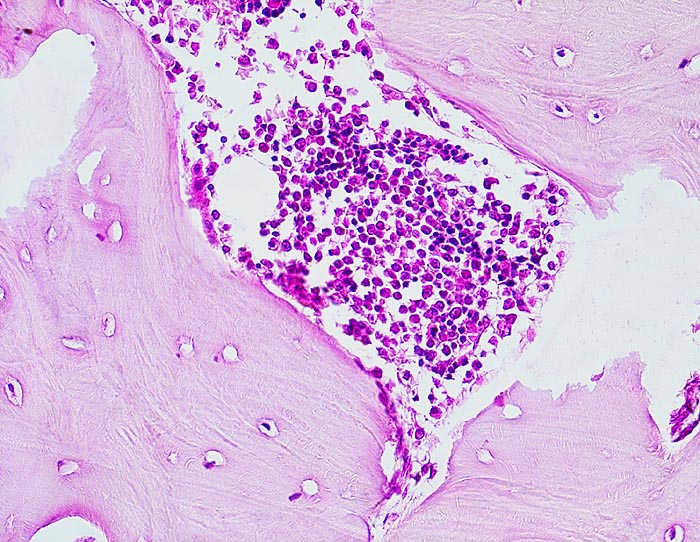

Normale Spongiosa

Normale Spongiosa mit wenig Osteoblasten an der Bälkchenoberfläche. Innerhalb der Spongiosa sind Osteozyten in ihren Lakunen erkennbar. Auf diesem Bild sind keine Osteoklasten zu sehen, die sich normalerweise an der Knochenoberfläche befinden und in Einbuchtungen liegen (sog. Howship Lakunen).

200